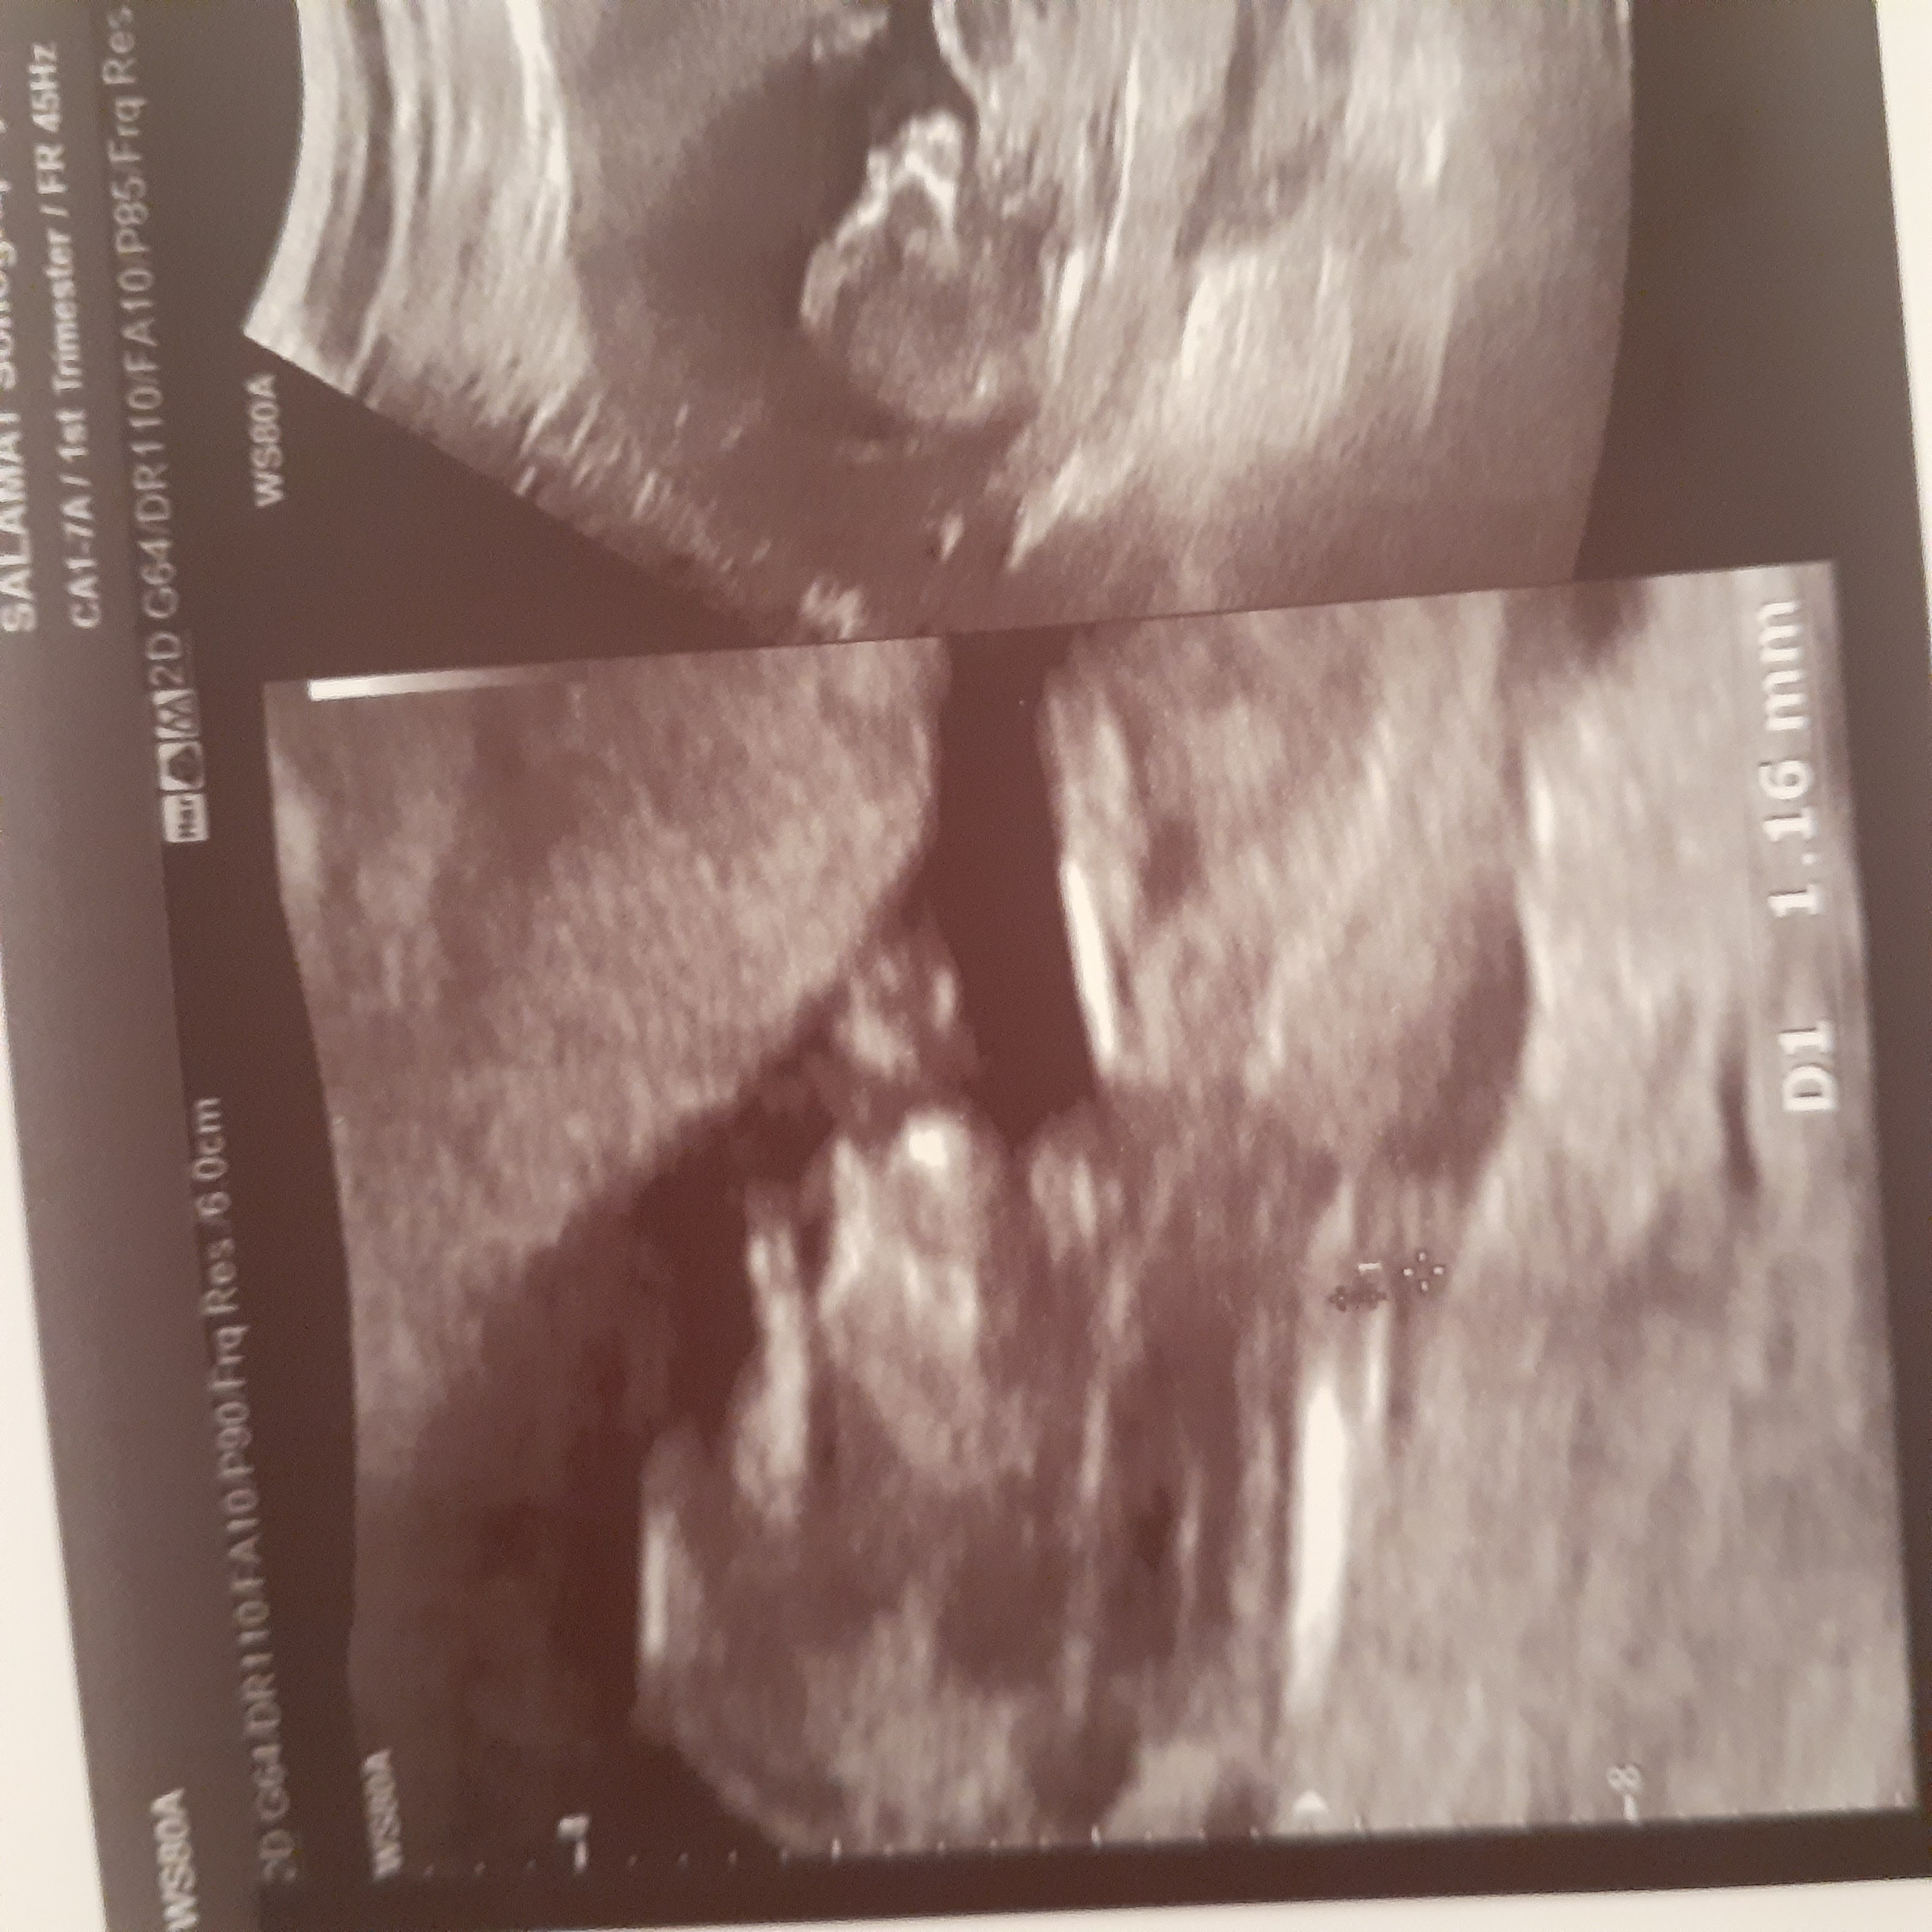

تفسیر سونوگرافی و ازمایشات و پاپ اسمیر